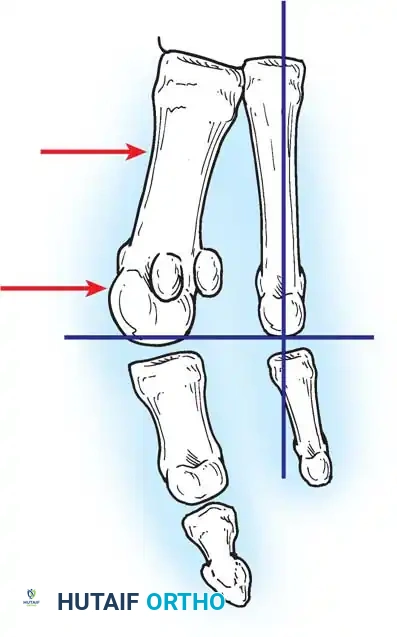

Hallux valgus (lateral deviation of the great toe) is not a single disorder, as the name implies, but a complex deformity of the fi rst ray that frequently is accompanied by deformity and symptoms in the lesser toes (Fig. 78-1). Often the angle between the fi rst and second metatarsals is more than the 8 to 9 degrees usually considered to be the upper limits of normal. The valgus angle of the fi rst metatarsophalangeal joint also is more than the 15 to 20 degrees considered to be the upper limits of normal (Fig. 78-2). If the valgus angle of the fi rst metatarsophalangeal joint exceeds 30 to 35 degrees, pronation of the great toe usually results. With this abnormal rotation, the abductor hallucis, which is normally plantar to the fl exion-extension axis of the fi rst metatarsophalangeal joint, moves further plantarward (Fig. 78-3). In this case, the only restraining medial structure is the medial capsular ligament with its capsulosesamoid portion (inserting into the base of the proximal phalanx) (Fig. 78-4) and capsulophalangeal portion (inserting into the plantar plate). The adductor hallucis, which is unopposed by the abductor hallucis, pulls the great toe further into valgus, stretching the medial capsular ligament (particularly the capsulosesamoid), attenuating this structure, and allowing the metatarsal head to drift medially from the sesamoids. In addition, the fl exor hallucis brevis, fl exor hallucis longus, adductor hallucis, and extensor hallucis longus increase the valgus moment at the metatarsophalangeal joint, further deforming the fi rst ray. The deep transverse intermetatarsal ligament runs between the plantar plates at the metatarsophalangeal joints and does not insert into bone on the adjacent sides of the metatarsal heads. Finally, the sesamoid ridge on the plantar surface of the fi rst metatarsal head (the crista) fl attens because of pressure (abutment) from the tibial sesamoid (Fig. 78-5). With this restraint lost, the fi bular sesamoid displaces partially or completely into the fi rst intermetatarsal space (see Fig. 78-2). In this situation, the patient is bearing less weight on the fi rst ray and more on the lesser metatarsal heads, increasing the likelihood of transfer metatarsalgia, callosities, and stress fracture of a lesser metatarsal.

Fig. 78-2 Hallux valgus complex. Note increase in intermetatarsal angle, lateral dislocation of sesamoids, subluxation of fi rst metatarsophalangeal joint (leaving metatarsal head uncovered), and pronation of great toe associated with marked hallux valgus.